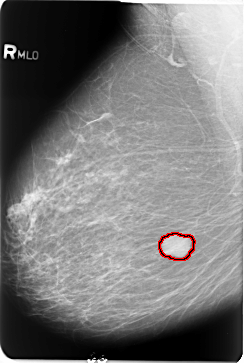

B_3484_1.RIGHT_MLO

FILE: B_3484_1.RIGHT_MLO.OVERLAY

TOTAL_ABNORMALITIES 1

ABNORMALITY 1

LESION_TYPE MASS SHAPE LOBULATED MARGINS CIRCUMSCRIBED

ASSESSMENT 4

SUBTLETY 5

PATHOLOGY BENIGN

TOTAL_OUTLINES 1

BOUNDARY